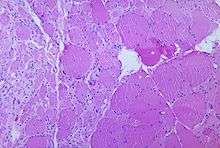

The destruction of neuronal cells produces lesions within the spinal ganglia; these may also occur in the reticular formation, vestibular nuclei, cerebellar vermis, and deep cerebellar nuclei.[36] Inflammation associated with nerve cell destruction often alters the color and appearance of the gray matter in the spinal column, causing it to appear reddish and swollen.[13] Other destructive changes associated with paralytic disease occur in the forebrain region, specifically the hypothalamus and thalamus.[36] The molecular mechanisms by which poliovirus causes paralytic disease are poorly understood.

- ↑ Karp, Dr. (18 March 2005). "A photomicrograph of the thoracic spinal cord depicting degenerative changes due to Polio Type III.". Public Health Image Library (PHIL). Centers for Disease Control and Prevention. Retrieved 24 January 2014.